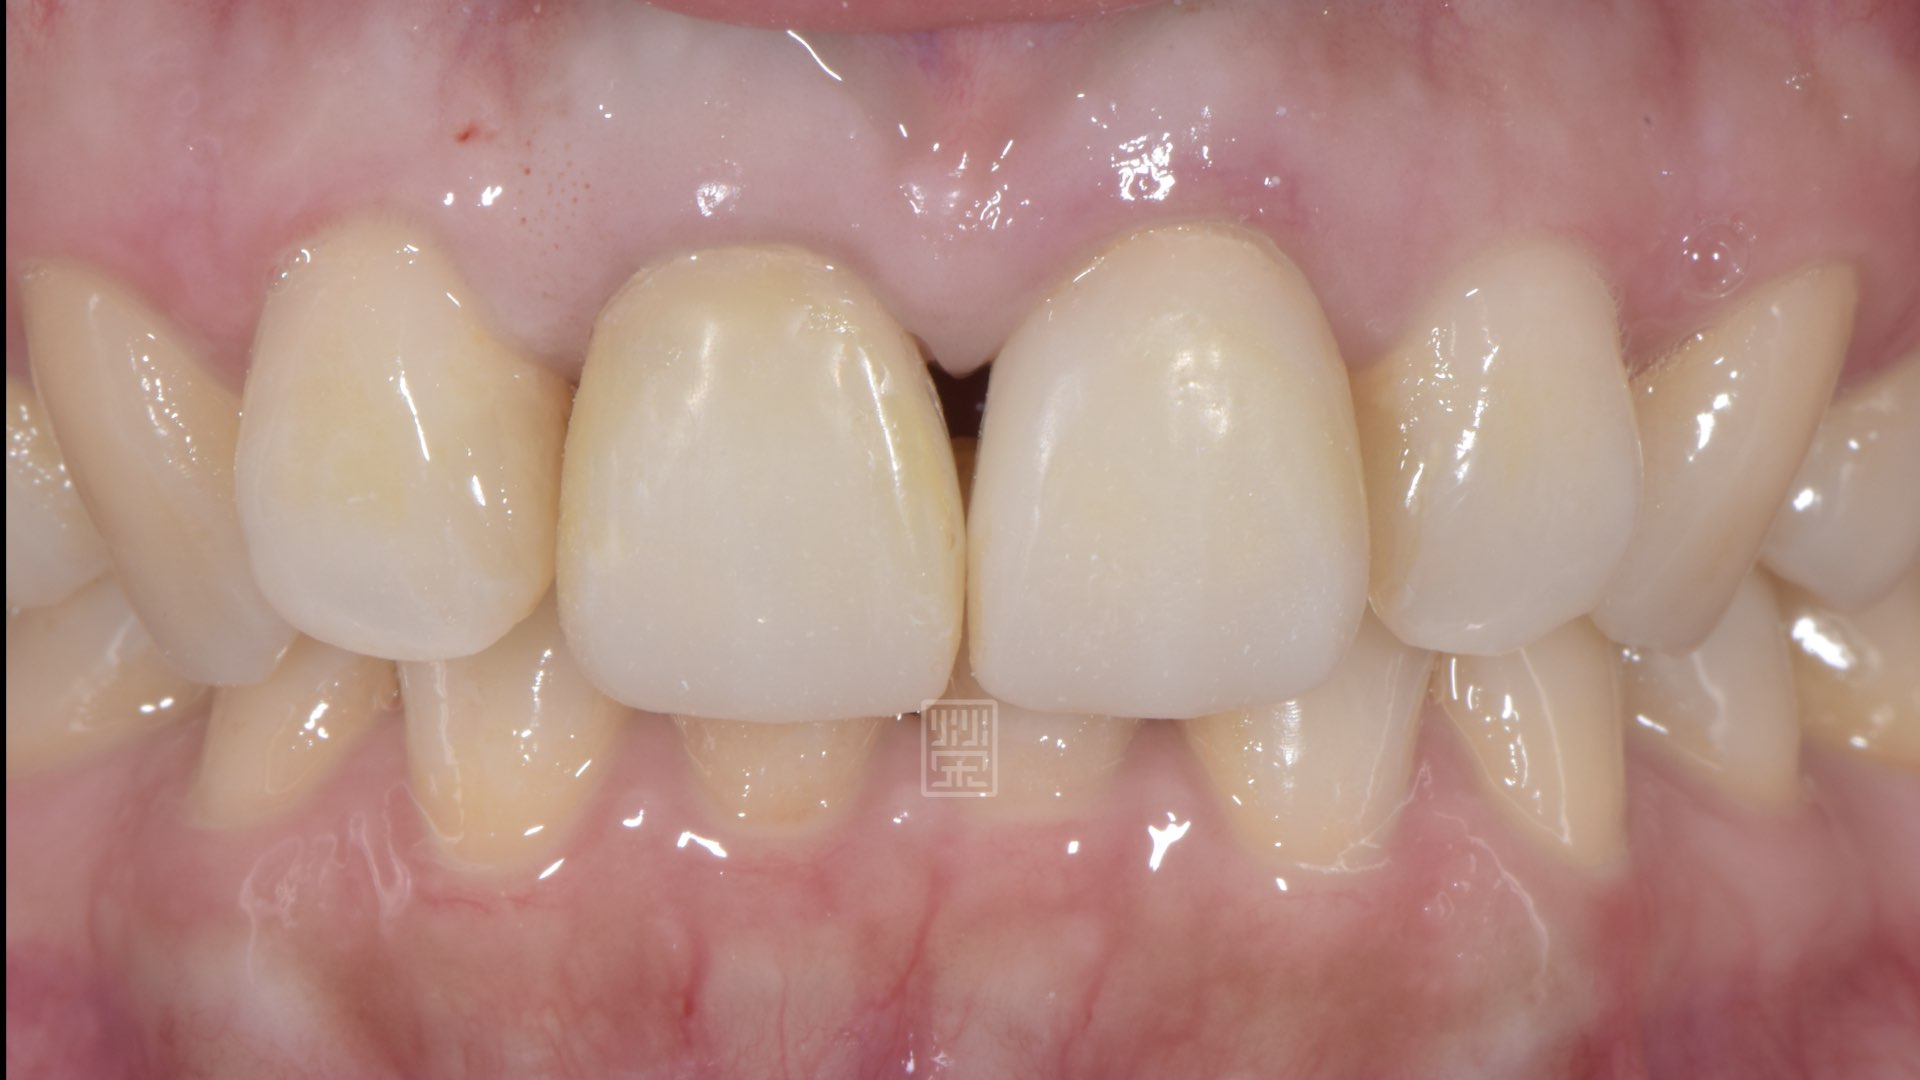

手術後癒合穩定

兩週後傷口修復